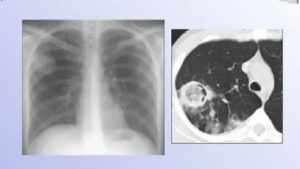

Важное значение в постановке диагноза имеет рентгенографическое обследование. На снимке патогены видны как округлые образования на поверхности легких. Взятие анализа мокроты больного позволяет определить вид грибкового возбудителя, что крайне важно для назначения будущего лечения.

Диагностические мероприятия, позволяющие выявить грибок в легкихМанипуляцияОписаниеРентгенологическое исследованиеПредоставляет возможность определить расположение очагов грибка в дыхательных органах.

Тем не менее, следует учитывать, что использование рентгенографии не считается эффективным диагностическим методом в случае грибкового поражения легочных тканей на ранних этапах течения патологии, так как имеется высокая вероятность диагностирования пневмонии хронического характера течения, опухоли, туберкулезной инфекции либо абсцесса. На поздних стадиях патологии при расшифровке рентген-снимка становятся заметными патологические изменения ребер, бронхиального древа и плевелы.

Применение компьютерных и визуальных методов в сочетании с анамнезом и клинической картиной позволяет поставить точный диагноз.

Чтобы исключить грибковый бронхит, проводят рентген, компьютерную томографию, бронхоскопию. Применение компьютерных и визуальных методов в сочетании с анамнезом и клинической картиной позволяет поставить точный диагноз.